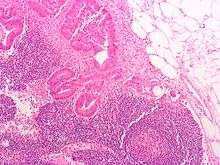

Section of small lymph node of rabbit.